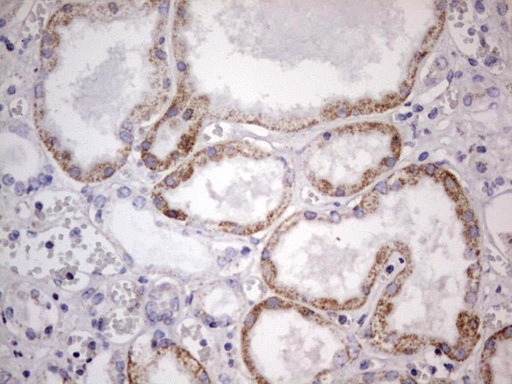

Immunohistochemical staining of paraffin-embedded Human Kidney tissue within the normal limits using anti-APC mouse monoclonal antibody. (M00008-2; heat-induced epitope retrieval by 1mM EDTA in 10mM Tris, pH8.5, 120°C for 3min)

Immunohistochemical staining of paraffin-embedded Human Kidney tissue within the normal limits using anti-APC mouse monoclonal antibody. (M00008-2; heat-induced epitope retrieval by 1mM EDTA in 10mM Tris, pH8.5, 120°C for 3min)